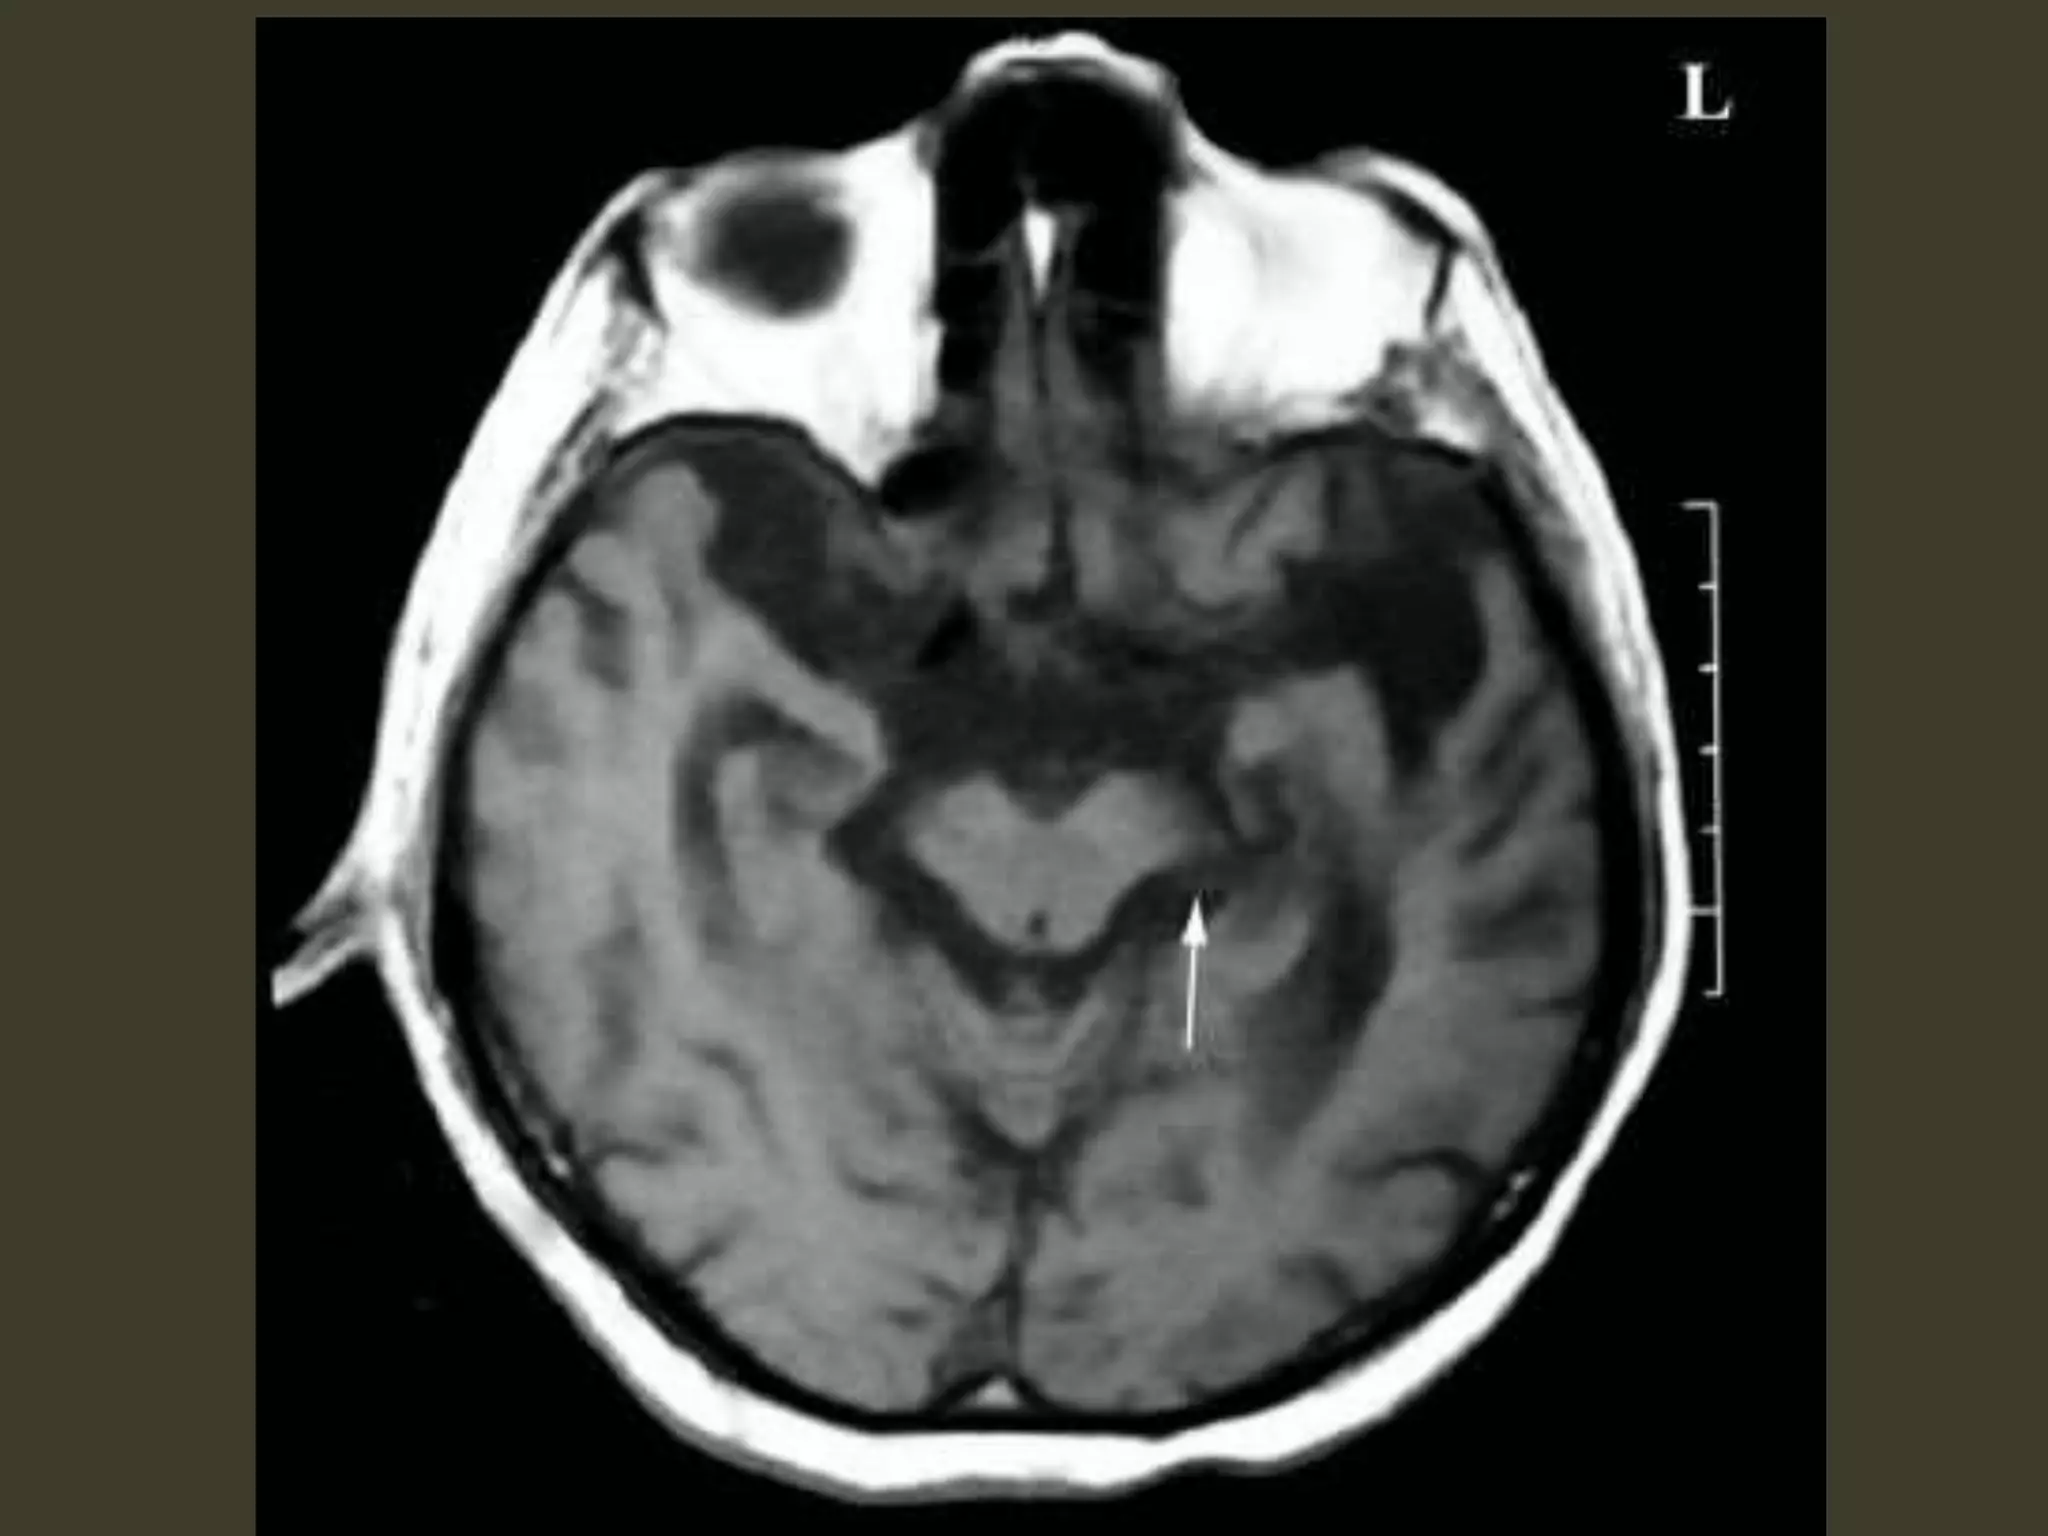

Subfalcine herniation: imaging Axialand coronal images show that •cingulate gyrus •anterior cerebral artery (ACA) •internal cerebral vein (ICV) are pushed from one side to the other under the falx cerebri. The ipsilateral ventricle appears compressed and displaced across the midline

Complications • unilateral obstructivehydrocephalus – foramen of Monro occlusion • Periventricular hypodensity with "blurred" margins of the lateral ventricle – Fluid accumulates in the periventricular white matter

Complications • When severe,the herniating ACA can be pinned against the inferior "free" margin of the falx cerebri 🡪 secondary infarction of the cingulate gyrus